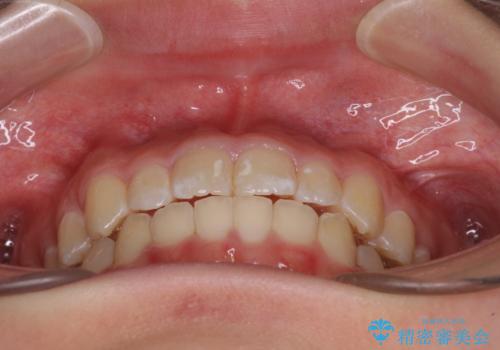

上下の骨幅を改善したことで、スムーズに歯列矯正を行うことができました。

インビザライン治療開始直後に遠方に引っ越しをされたため、通院間隔が長くなり、治療期間が長くなりましたが、しっかりと治療を行うことができました。